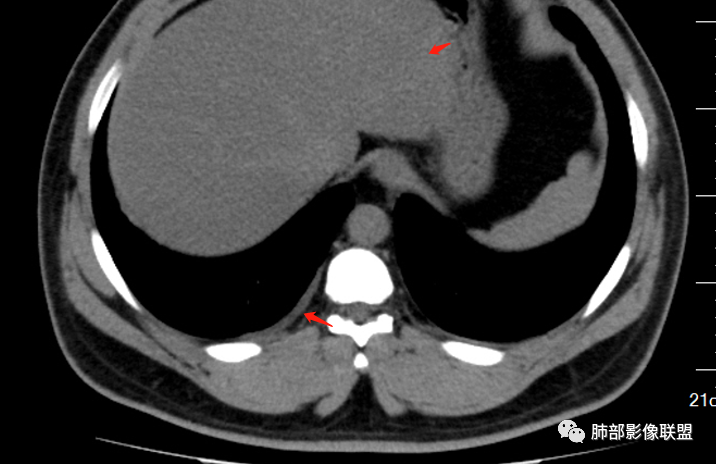

男32岁。既往曾发现血肌酐升高.此次因左足痛6天入院。有痛风、高血压病史。两肺弥漫性的病变,小片状或者结节状为主病变,小叶中心分部为主,边界不清。心影比较饱满,肝实质密度均匀的降低。考虑为肝损害的影像学改变。综合考虑多功能脏器的损害,肺部损害肺泡炎?肺水肿?或病毒性的肺炎?

少量积液,脂肪肝

转移性钙化继发于甲旁亢和慢性肾衰

磷酸钙沉积在肺泡间隔

间质,肺泡间隔

继发甲状旁腺机能亢进?骨钙?

甲旁亢,肾功能不全,都可以发生